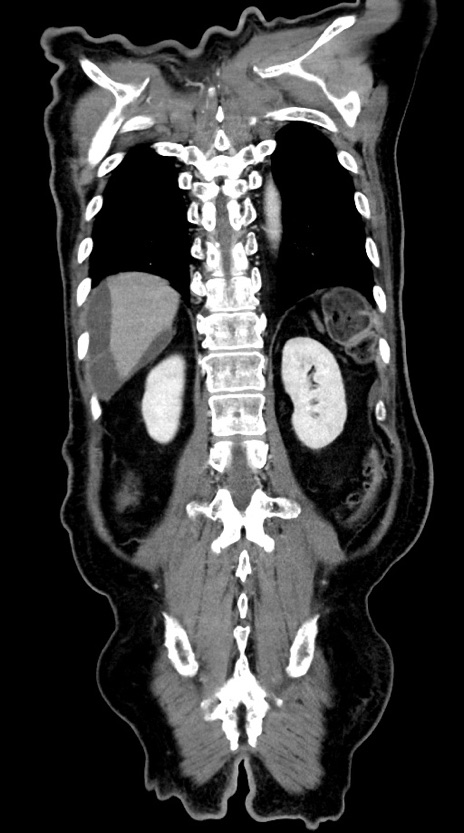

症例28(冠状断像)

【症例】60歳代男性

【主訴】嘔吐

【現病歴】胃癌にて胃全摘後。食思不振が悪化し、夜中に嘔吐することがある。

【既往歴】胃癌、胃全摘、脾摘、胆摘後

【データ】WBC 5900、CRP 10.56